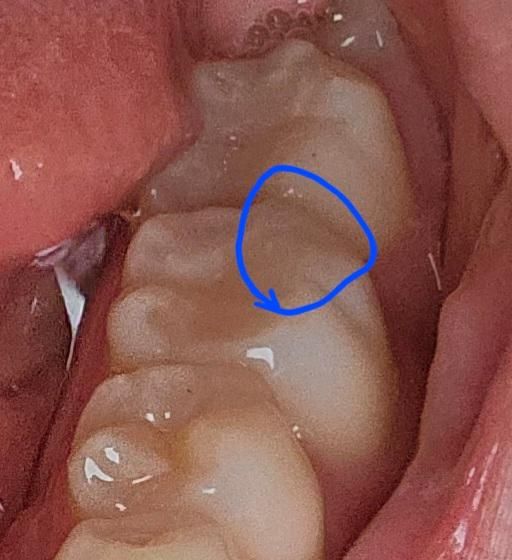

레진치료할 때 실수로 치아를 더 깎은 거 같아요

오늘 레진치료를 받았는데 받는 도중에 드릴이 일정한 소리를 내다가 살짝 미끄러지는 소리가 났어요 순간 뭐지? 싶었는데 가만히 있었는데 치료를 받고 나와서 그쪽 이를 만져보니 바깥쪽이 깎인 느낌이었어요 지금까지 레진치료를 받으면 치아 바깥쪽은 변화가 없고 안쪽만 레진으로 바뀐 느낌이었는데요 집에가서 확인해보니 그쪽이 살짝 깎여있는 게 보여요 위쪽부분이라 신경하고는 안 가까워서 문제는 없지만 쓸데없이 치아를 깎였다는 생각때문에 너무 속상하고 이미 깎였는데 뭘 어떻게 보상받을수도 없고 너무 속상합니다 이런 경우 치과의사한테 말해봤자 치료를 위해서 깎은거라고 변명할 거 같아서 어떻게 해야할지도 모르겠습니다

• 1번 째 사진

저부위는 충치가 없는 부위라면 삭제를 하는곳은 일반적이지 않습니다. 원래 저랫거나 삭제를 햇다면 충치가 잇어서 제거를 햇을것같습니다.

이전 사진이 없어 정확하게 말씀은 못드리겠으나 치과용 드릴로 깎인 모양새는 아닙니다. 만일 드릴이 그쪽을 지나가서 갈아낸 거라면 치료 중 스친 정도일 것 같은데 정말 거의 치아에는 기능적으로는 영향 없습니다. 걱정마세요